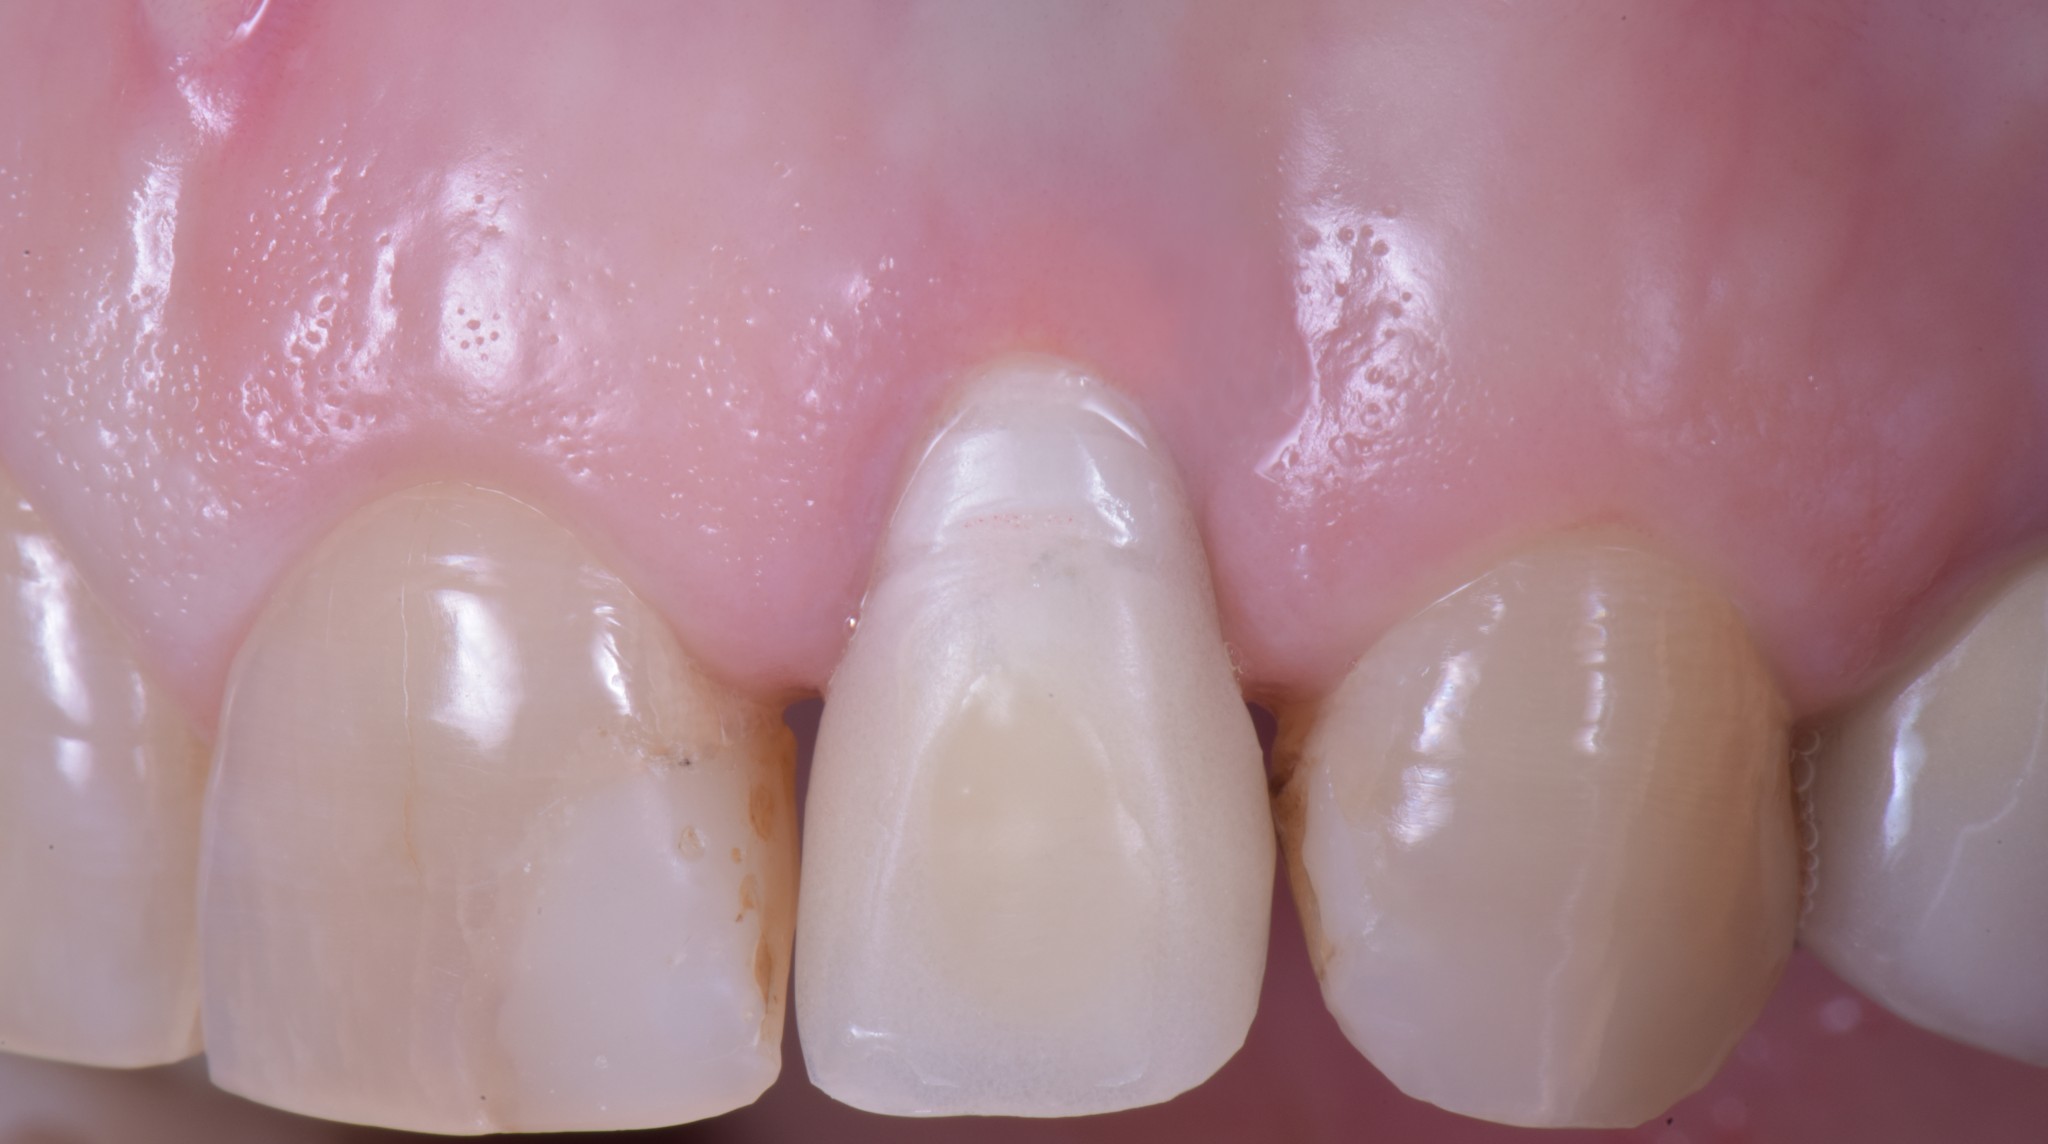

corso gestione tessuti molli - guarigione 1

corso gestione dei tessuti molli - guarigione 2

Ti mostro la foto a sette giorni per due motivi.

• La bellezza di una chirurgia si valuta dalla guarigione a sette giorni. Se aspetti 2 anni, alla fine anche una chirurgia di merda guarisce.

• Ho operato la paziente 7 giorni fa e non ho foto più recenti ma penso che concorderai con me che dopo una guarigione così difficilmente avremo delle sorprese.

Come puoi vedere abbiamo risolto completamente il deficit dei tessuti molli che era stato lasciato dopo le precedenti terapie e…

… posto le basi per una nuova riabilitazione definitiva che si possa definire esteticamente degna dei tempi in cui abbiamo la fortuna di vivere.